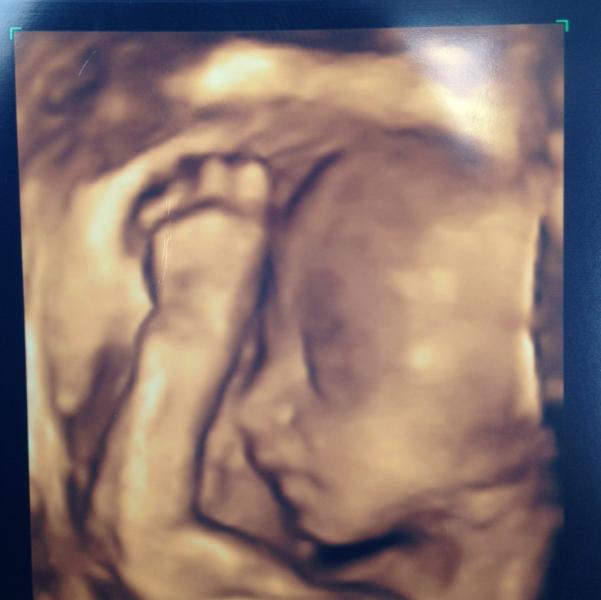

А вот и моя доченька на 4Д УЗИ 😃крошка такая, я ожидала увидеть ребёнка постарше 😃 спала наша девочка, врач теребила мой живот, чтобы разбудить, а она руку под голову подтянет и дальше спит 😏 так что лицо увидели только вот так, в профиль... 24 недели, 630 грамм

Прекрасное фото . Как раз сейчас на этих неделях 22-28 очень хорошо видны детки . Моя себя показала так отчётливо в 22 недели . И всё ... на всех следующих УЗИ , она постоянно отворачивалась , :( , а я ждала всегда УЗИ как манну небесную :) . Как же это трогательно 😌, эх беременность , чудесная пора .

Потрясающие фото! Такой носик остренький!! Перебирала сейчас все свои распечатки с узи, и нет ни одной достойной "для рамочки" везде какие-то непонятные разводы, которые не все беременные то разберут, только врачи😁. Думаю, может внепланово на "фотосессию" записаться)